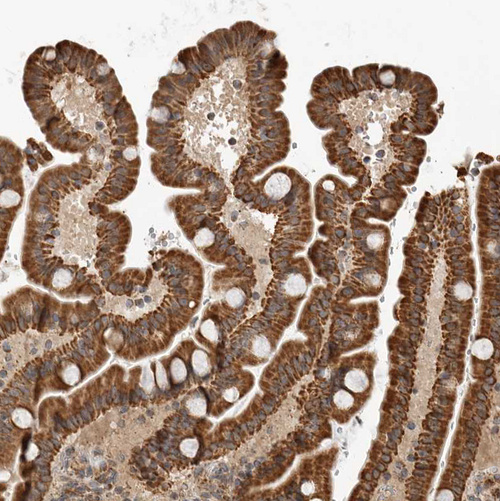

Immunohistochemical staining of human Prostate shows strong granular cytoplasmic positivity in glandular cells.